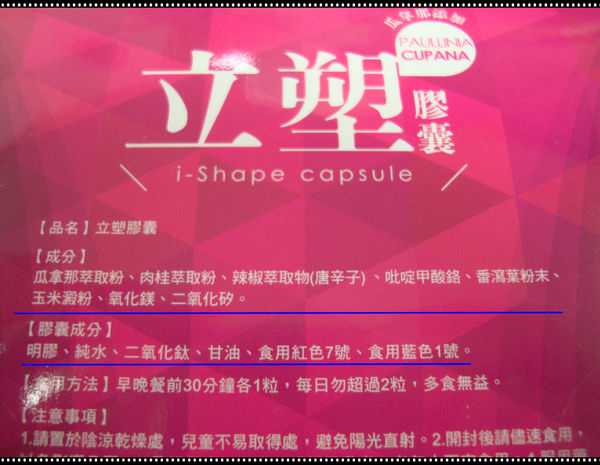

Supercut塑魔纖立塑膠囊的成分有:瓜拿那萃取粉、肉桂萃取粉、辣椒萃取物(唐辛子)、吡啶甲酸鉻、番瀉葉粉末、玉米澱粉、氧化鎂、二氧化矽。

之前上過相關課程,成分表是依照每項成分的多寡來排列順序,排在最前面的就是產品的主要成分!

那我就跟大家分享瓜拿那萃取粉、肉桂萃取粉和辣椒萃取物吧

瓜拿那萃取和辣椒萃取是可以幫助纖體瘦身常見的營養素!

1.「瓜拿那」是原產於亞馬遜流域的一種藤蔓植物,富含酵素可以幫助排便順暢,並且能抑制脂肪分解酵素,此外也有降低食慾的效果喔~~萃取物中含有天然咖啡因,可以提高新陳代謝率以及排出多餘水分!

2.「辣椒萃取物」則是可以幫助體內脂肪燃燒、增加卡路里的消耗,達到防止脂肪積聚的效果

3.「肉桂萃取物」看到肉桂,就想到麥當勞的蘋果派或是手掌麵包,雖然很多人很害怕那味道,但艾哥愛死肉桂了!!!!肉桂在古代被視為是最有價值的東方香料之ㄧ,中世紀時,肉桂的聲望僅次於昂貴的黑胡椒,除了香料和薰香價值, 傳統上肉也被用來治療消化不良、脹氣、關節疼痛、出血和經痛,研究也指出肉桂可以促進新陳代謝喔

食用方式:早晚餐前30分鐘各1粒,每日不超過2粒。(多食無益)

番瀉葉萃取物每日食用限量為12mg以下,

番瀉葉萃取物每日食用限量為12mg以下,